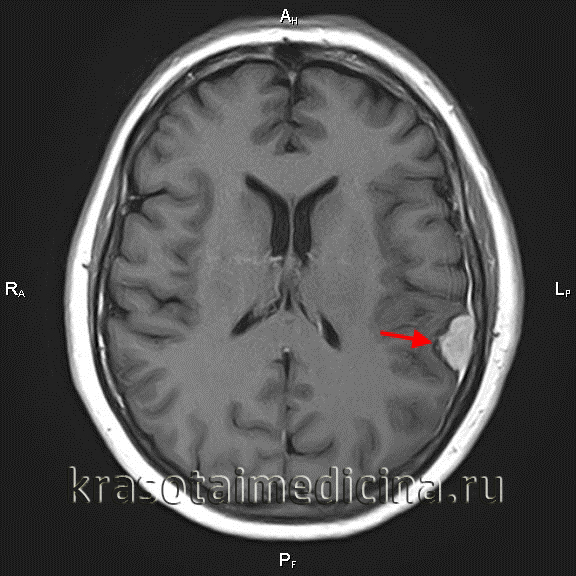

МРТ головного мозга (С+). Объемное образование в теменной области слева, широким основанием прилежащее к мягкой оболочке

Обязательным в диагностике менингиомы является назначение томографических методов исследования. МРТ головного мозга позволяет определить наличие объемного образования, спаянность опухоли с твердой мозговой оболочкой, помогает визуализировать состояние окружающих тканей. При МРТ в Т1 режиме сигнал от опухоли схож с сигналом от мозга, в режиме Т2 выявляется гиперинтенсивный сигнал, а также отек мозга. МРТ может применяться во время операции для контроля удаления всей опухоли и для того, чтобы получить материал для гистологического исследования. МР спектроскопия применяется для определения химического профиля опухоли.